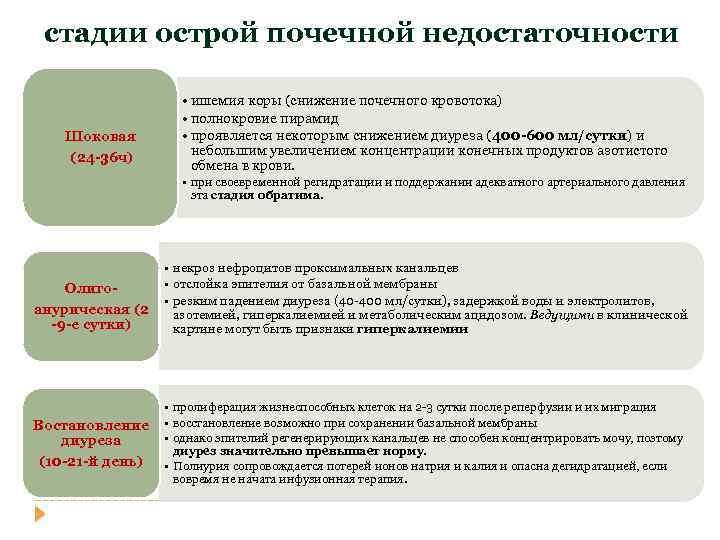

стадии острой почечной недостаточности Шоковая (24 -36 ч) • ишемия коры (снижение почечного кровотока) • полнокровие пирамид • проявляется некоторым снижением диуреза (400 -600 мл/сутки) и небольшим увеличением концентрации конечных продуктов азотистого обмена в крови. • при своевременной регидратации и поддержании адекватного артериального давления эта стадия обратима. Олигоанурическая (2 -9 -е сутки) Востановление диуреза (10 -21 -й день) • некроз нефроцитов проксимальных канальцев • отслойка эпителия от базальной мембраны • резким падением диуреза (40 -400 мл/сутки), задержкой воды и электролитов, азотемией, гиперкалиемией и метаболическим ацидозом. Ведущими в клинической картине могут быть признаки гиперкалиемии • пролиферация жизнеспособных клеток на 2 -3 сутки после реперфузии и их миграция • восстановление возможно при сохранении базальной мембраны • однако эпителий регенерирующих канальцев не способен концентрировать мочу, поэтому диурез значительно превышает норму. • Полиурия сопровождается потерей ионов натрия и калия и опасна дегидратацией, если вовремя не начата инфузионная терапия.